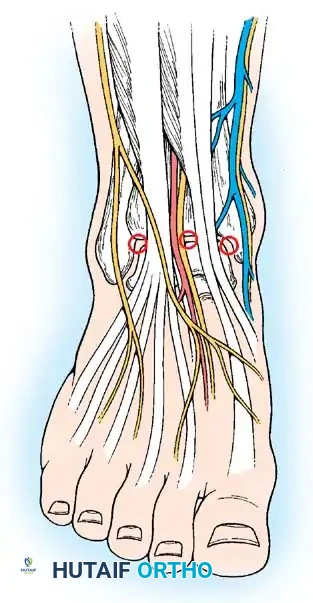

Arthroscopic Portal Placement and Neurovascular Anatomy

A profound, three-dimensional understanding of the anatomy surrounding the ankle joint is the most critical prerequisite for safe ankle arthroscopy. The superficial neurovascular structures must be meticulously identified, palpated, and outlined with a surgical marking pen prior to the induction of regional or general anesthesia, or immediately after exsanguination.

Anterior Portals

The anterior compartment of the ankle is accessed primarily through the anterolateral and anteromedial portals.

Anterior portals diagram illustrating the critical relationship between the portals and the anterior neurovascular bundles.

1. Anterolateral Portal

* Location: Located at the level of the tibiotalar joint line, immediately lateral to the peroneus tertius tendon.

* Structure at Risk: The intermediate dorsal cutaneous branch of the superficial peroneal nerve.

* Clinical Pearl: Injury to this nerve can be reliably avoided by plantarflexing and inverting the foot. This maneuver places the nerve under tension, allowing it to be visually identified or palpated as a subcutaneous cord prior to incision.

2. Anteromedial Portal

* Location: Located at the joint line, immediately medial to the anterior tibial tendon.

* Structure at Risk: The great saphenous vein and the saphenous nerve.

* Clinical Pearl: Injury is avoided by keeping the incision strictly adjacent to the medial border of the tibialis anterior tendon and avoiding medial drift during trocar insertion.

3. Anterocentral Portal (Not Recommended)

* Location: Located just lateral to the extensor hallucis longus (EHL) tendon or between the tendons of the extensor digitorum communis (EDC).

* Structure at Risk: The dorsalis pedis artery and the deep branch of the peroneal nerve.

* Consensus: Routine use of this portal is strongly discouraged due to the unacceptably high risk of catastrophic neurovascular injury. If absolutely necessary, blunt dissection is mandatory. Most master surgeons find no clinical necessity for this portal.